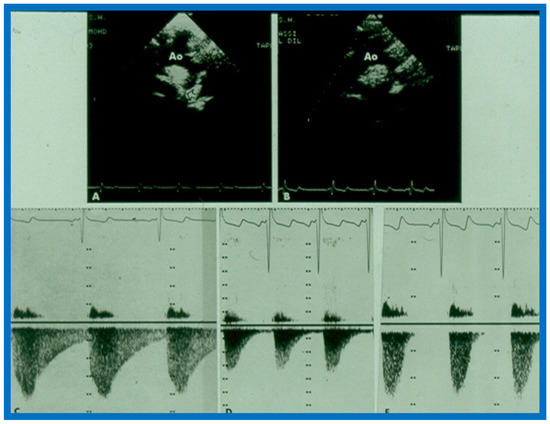

16. Echo-Doppler Studies in the Evaluation of the Results of Balloon Angioplasty of Aortic Coarctation

This study sought to appraise the usefulness of echo-Doppler studies in evaluating immediate and follow-up results of balloon angioplasty of native aortic coarctation [17]. Echo-Doppler data prior to and immediately following angioplasty were available for 19 infants and children, and such data at follow-up (3 to 22 months; mean 12 months) were accessible for review in 18 patients. There was no significant change (p > 0.1) in left ventricular (LV) end-diastolic dimension, LV posterior wall thickness in diastole and LV shortening fraction either immediately after balloon angioplasty or at follow-up. However, the Doppler flow velocity (3.2 ± 0.85 vs. 2.5 ± 0.5 m/s) and the calculated pressure gradients (∆P = 4V2) across the coarctation 43.3 ± 21.9 vs. 26.5 ± 10.3 mmHg) decreased immediately after (p < 0.01) balloon angioplasty, as well as at follow-up (p < 0.02). But there was not a good correlation between the Doppler derived and catheterization-measured gradients (r = 0.49–0.78). It was also observed that pandiastolic anterograde descending aortic flow shortened/disappeared (Figure 53 and Figure 54) in all patients who had successful balloon angioplasty. It was concluded that echo-Doppler studies are useful in demonstrating effectiveness of relief of aortic obstruction by balloon angioplasty, but are not predictive of exact residual gradients. This prompted us to conduct more extensive study to evaluate this issue [18], which will be discussed in the next section.

Figure 53.

Continuous wave Doppler flow velocity recordings from suprasternal notch view directing the Doppler signal towards the descending aorta prior to (top) and twelve hours following (bottom) balloon angioplasty of aortic coarctation. Note the reduction of peak Doppler flow velocity from 3.47 m/s to 2.35 m/s after balloon angioplasty. Also note that the pandiastolic flow seen prior to angioplasty is no longer seen after angioplasty. Reproduced from Rao P.S. [17].

Figure 54.

(A,B) Two-dimensional (2D) echo images prior to (A) and following (B) balloon angioplasty of aortic coarctation show improvement in (B). (C–E) Continuous wave Doppler flow velocity recordings from suprasternal notch directing the Doppler signal towards the descending aorta prior to (C) and immediately following (D) balloon angioplasty of aortic coarctation and at six months after angioplasty (E) are shown. Note the reduction of peak Doppler flow velocity from (C) to (D) with further fall in (E). Also note that the diastolic flow is seen throughout the entire diastole (pandiastolic) prior to angioplasty (C), and is seen only is early diastole immediately after angioplasty (D) and at six-month follow-up (E), there was no diastolic flow at all. Reproduced from Rao P.S. [17].